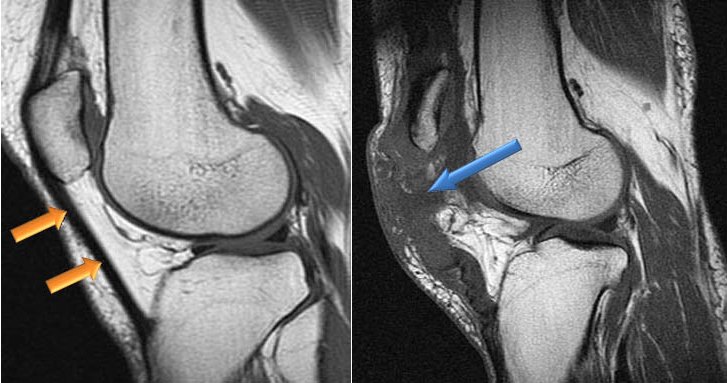

- Ультразвуковое исследование. С помощью УЗИ можно оценить состояние связок и сухожилий.

- Магнитно-резонансная томография. Эффективный способ, позволяющий точно установить причину патологии. МРТ дает возможность оценить качественные и количественные характеристики повреждений волокон соединительных тканей.